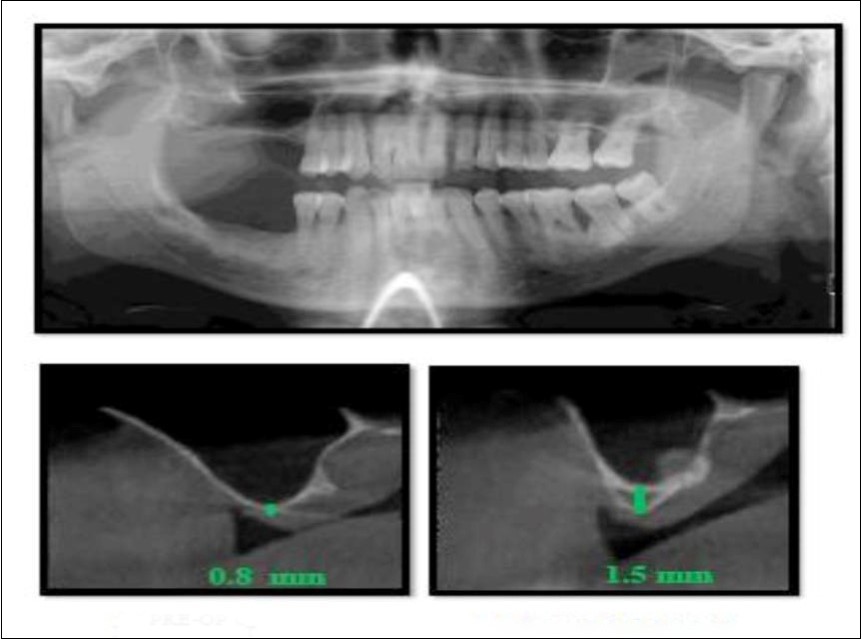

With a pre-operative residual bone height of 0.8 mm in 16 region and 1.5 mm in 17 region, direct sinus augmentation was carried-out in a 40 year old male patient followed by implant placement of 3.75 x 11.5 dimensions as a single step procedure. Lateral window was created and synthetic graft material was dispensed through the lateral osteotomy site to maintain the elevated sinus membrane followed by placement of two dental implants through the crestal approach measuring 3.75 x 11.5 mm under local anesthesia and strict aseptic protocols. At the end of 6 months, a CBCT scan was advised to evaluate the increase in bone height which was 11 mm and 10.8 mm in 16 and 17 region respectively. (Figure 1, Figure 2)

Figure 1.Pre-operative Orthopantomograph and cross sections of CBCT showing residual alveolar bone height